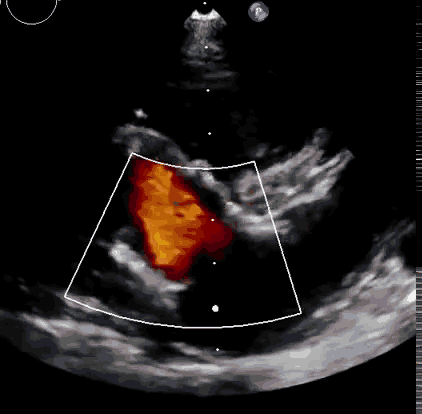

本次臨床前研究經右側頸靜脈置入LuX-Valve Plus輸送系統(tǒng)可調彎鞘管,在DSA及超聲引導下將人工三尖瓣瓣膜植入到原有三尖瓣位置,利用獨特的錨定技術將人工瓣膜支架可靠固定在預定的位置。

上海中山醫(yī)院葛均波院士、錢菊英院長、周達新教授、潘文志教授、潘翠珍教授、李偉教授共同完成此次臨床前研究。術后葛均波院士對Lux-Valve Plus的器械操作性能給予了高度評價,DSA和超聲影像也顯示出在本次研究中Lux-Valve Plus的安全性和有效性俱佳。